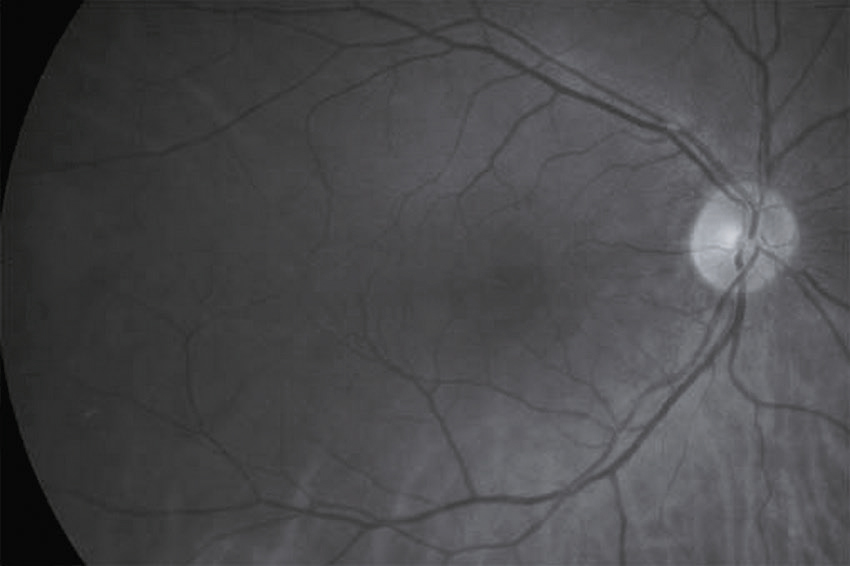

Vous réalisez un fond d’œil. L’œil droit est présenté ci-dessous (fig. 31.5). Quelle(s) est (sont) votre (vos) conclusion(s) ?

L'image montre une photographie en noir et blanc de la rétine humaine, probablement prise lors d'un examen ophtalmologique. La rétine est la couche de tissu sensible à la lumière située à l'arrière de l'œil. On peut observer plusieurs vaisseaux sanguins qui se ramifient à partir du disque optique, une zone circulaire claire située à droite de l'image. Le disque optique est l'endroit où le nerf optique quitte l'œil pour transmettre les informations visuelles au cerveau. Les vaisseaux sanguins apparaissent comme des lignes sombres qui se ramifient et se dispersent à travers la rétine. Cette image permet aux professionnels de la santé de détecter des anomalies ou des maladies oculaires telles que la rétinopathie diabétique, le glaucome ou la dégénérescence maculaire. En examinant attentivement la rétine et les vaisseaux sanguins, les médecins peuvent évaluer la santé de l'œil et diagnostiquer des conditions qui pourraient affecter la vision.

- A œdème papillaire

- B atrophie papillaire

- C macula rouge cerise

- D hémorragies en flammèches

- E normal